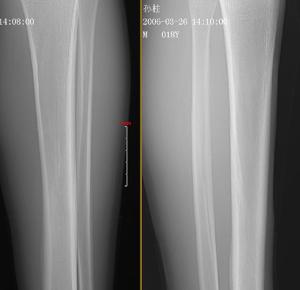

考虑右胫骨上段疲劳骨折一例

看图说话胫骨疲劳性骨折